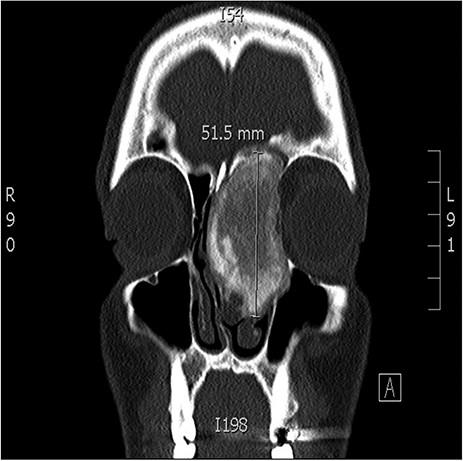

A 34-years-old man presented with left-sided facial pain, headache and nasal obstruction for a long duration, with no history of bleeding per nose, nor blurring of vision. Upon examination, there was a large left nasal cavity bony outgrowth pushing the middle turbinate and pushing the nasal septum to the right side (Fig. 1). CT scan of the paranasal sinuses showed a large mass centered in the left anterior ethmoid sinus, the mass measures 3.7 × 2.9 cm (trans-axial) (Fig. 2) and 3.7 × 5.2 cm (coronal) (Fig. 3), it has a heterogeneous density with calcified and soft-tissue component. The calcified component is in the periphery with central soft tissue density. The mass resulted in remodeling of adjacent bones with nasal septal deviation to the right, it extended superiorly to involve the frontal sinuses as well as invading the left cribriform plate and intracranial extension (Fig. 4), it extended inferiorly displacing the medial wall of the left maxillary antrum. The medial aspect of the mass caused remodeling of the medial wall of the left orbital cavity with bulging and displacement of the medial rectus muscle. The mass resulted in obstruction of the left frontal sinus.

Coronal CT image of the sinuses showing a large mass obstructing the frontal sinus.

Coronal CT image of the sinuses showing a mass encroaching the orbit and skull base.